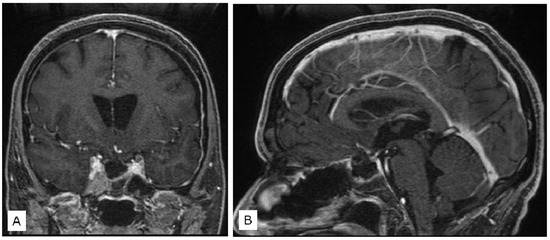

3.1.1. Case 1